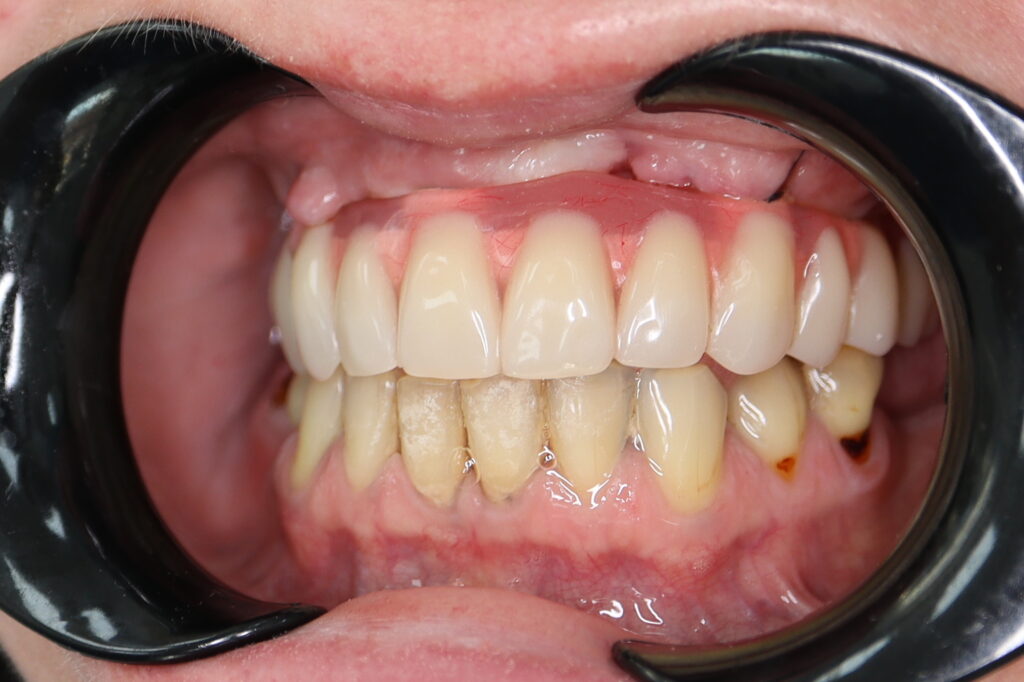

Ситуация до лечения

Жалобы: Пациент обратился с целью тотальной имплантации верхней челюсти.

Диагноз: Частичная вторичная адентия верхней челюсти.

пациент до тотальной имплантации